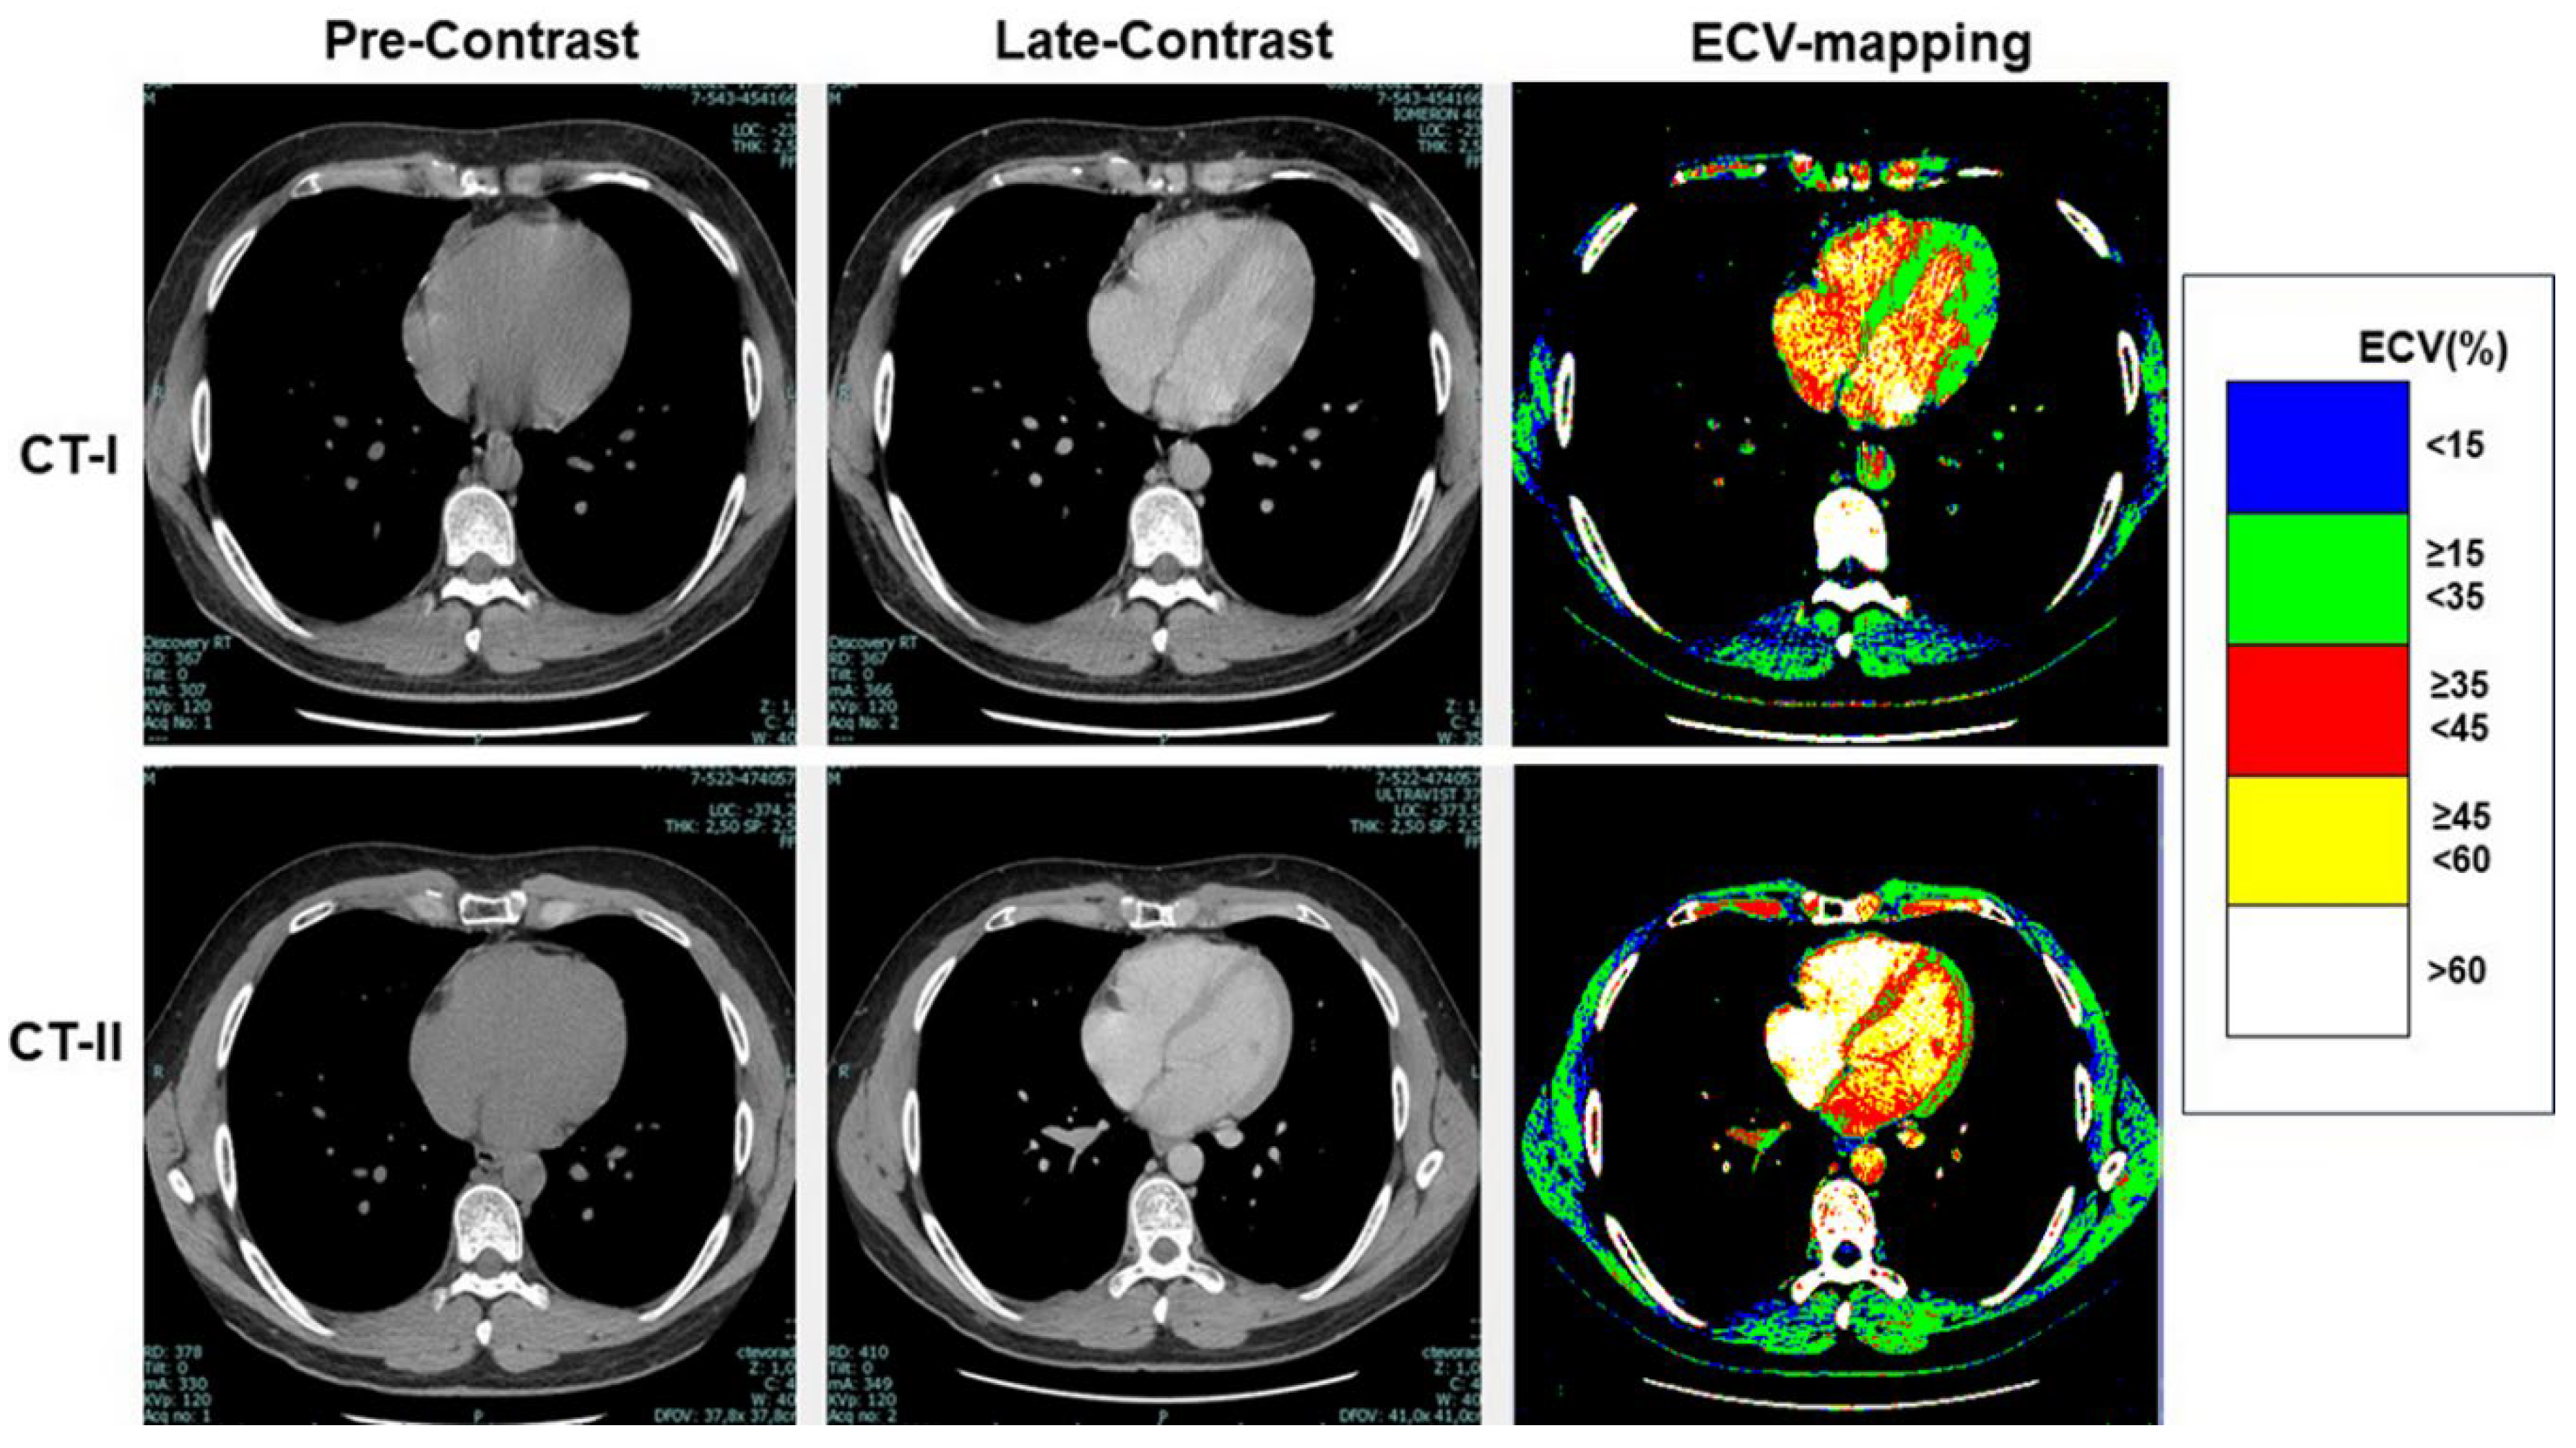

As shown in Table 3, at CT-I myocardial ECV measured in the interventricular septum and in the LV lateral wall was not significantly between High-risk and Low-risk groups, despite age and gender differences between them. Similarly, ECV of both the septum and LV lateral wall was not significantly different between the groups at CT-II. Examples of ECV maps are shown in Figure 1, Figure 2 and Figure 3.

Figure 2. ECV mapping in a patient undergoing a Low-risk chemotherapy protocol. ECV maps of CT-I (right upper panel) and CT-II (right lower panel) are comparable.

Figure 3. ECV mapping in a patient undergoing a High-risk chemotherapy protocol. A diffuse increase of ECV can be seen at CT-II (right upper panel) compared to CT-I (right lower panel).